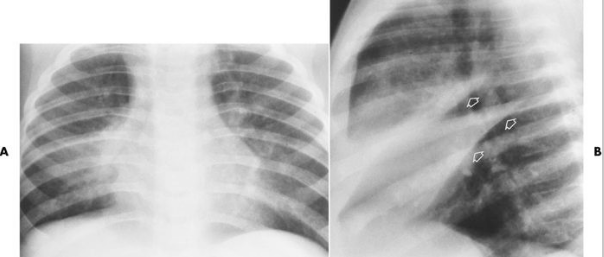

Describe the RA for alveolar pneumonia (this pic and pic in description)

homogenous consolidation in segments or the entire lung — air bronchograms are present (when an entire lobe fills with fluid but has not collapsed)

Describe the RA of bronchopneumonia

inflammation produces small patches of consolidation throughout the lungs — no air bronchograms present

Describe the RA of interstitial pneumonia

mesh-like shadows resulting from linear or reticular opacities — untreated can lead to “honeycomb lung” or cystic spaces as demonstrated by CT

PT is 43 yr old male presenting with productive cough and fever/chills

What pathology is present?

pneumonia — alveolar/pneumococcal pattern